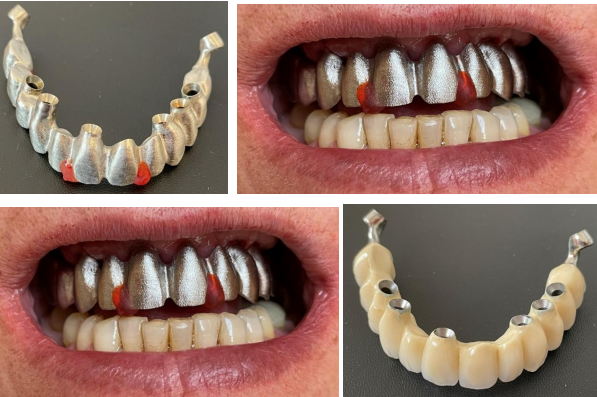

After consultation, plan was made as follows: to extract remaining teeth in the maxilla and mandible, the existing crowns on implants in the mandible were to be changed to have the same color for all the teeth (Vita B1) in the mouth Fig 1.

Figure 1 shows the panoramic radiograph and clinical photo at presentation.

On the second appointment the verification key was tried in, bite relation as well as aesthetical outcome were checked and validated. Ten days later frame was tried in Figure 4.

The metal ceramic bridges were placed in the mandible and maxilla10 days after frame try-in.

The bridge in the maxilla is in 2 parts and screw retained, here angulated screw channels were used in order to get  perfect fit.  In the mandible the bridge is screw and cement retained.

Figure 4: Laboratory steps: frame try-in and metal-ceramic bridge

Three weeks after initial consultation, patient´s mouth was rehabilitated with definitive metal ceramic bridges. This was made possible due to the achieved bicortical anchorage in the anterior part and a strong cortical anchorage at the pterygoid plates  (75 N/cm) in the maxilla,  these anchorage ensured high primary stability which encourages immediate loading. Fig 5

Figure 5: Clinical photograph and the panoramic radiograph of patient and after bridge delivery, day of placement